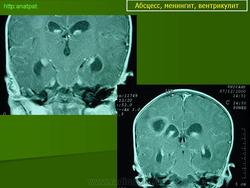

Абсцесс головного мозга – это очаговое скопление гноя в мозговом веществе, окруженное капсулой.

Абсцессы могут локализоваться в различных участках мозгового вещества. Обычно абсцессы сочетаются с менингоэнцефалитами, энцефалитами, сопровождаются повышением температуры тела, воспалительными изменениями крови и ликвора. Клиническая картина разнообразна и состоит из различных сочетаний общемозговых симптомов (головной боли, головокружения, тошноты, рвоты, нарушений сознания), менингеальной (оболочечной) и очаговой неврологической симптоматики.

Компьютерная (КТ) или магнитно-резонансная (МРТ) томография головного мозга являются ведущими методами диагностики посттравматических абсцессов, позволяющих судить об их расположении, объеме, структуре, консистенции, содержимом, воздействии на вещество головного мозга. Для исключения опухолей головного мозга, туберкулом, паразитарных заболеваний проводится ОФЭКТ (однофотонная эмиссионная компьютерная томография).